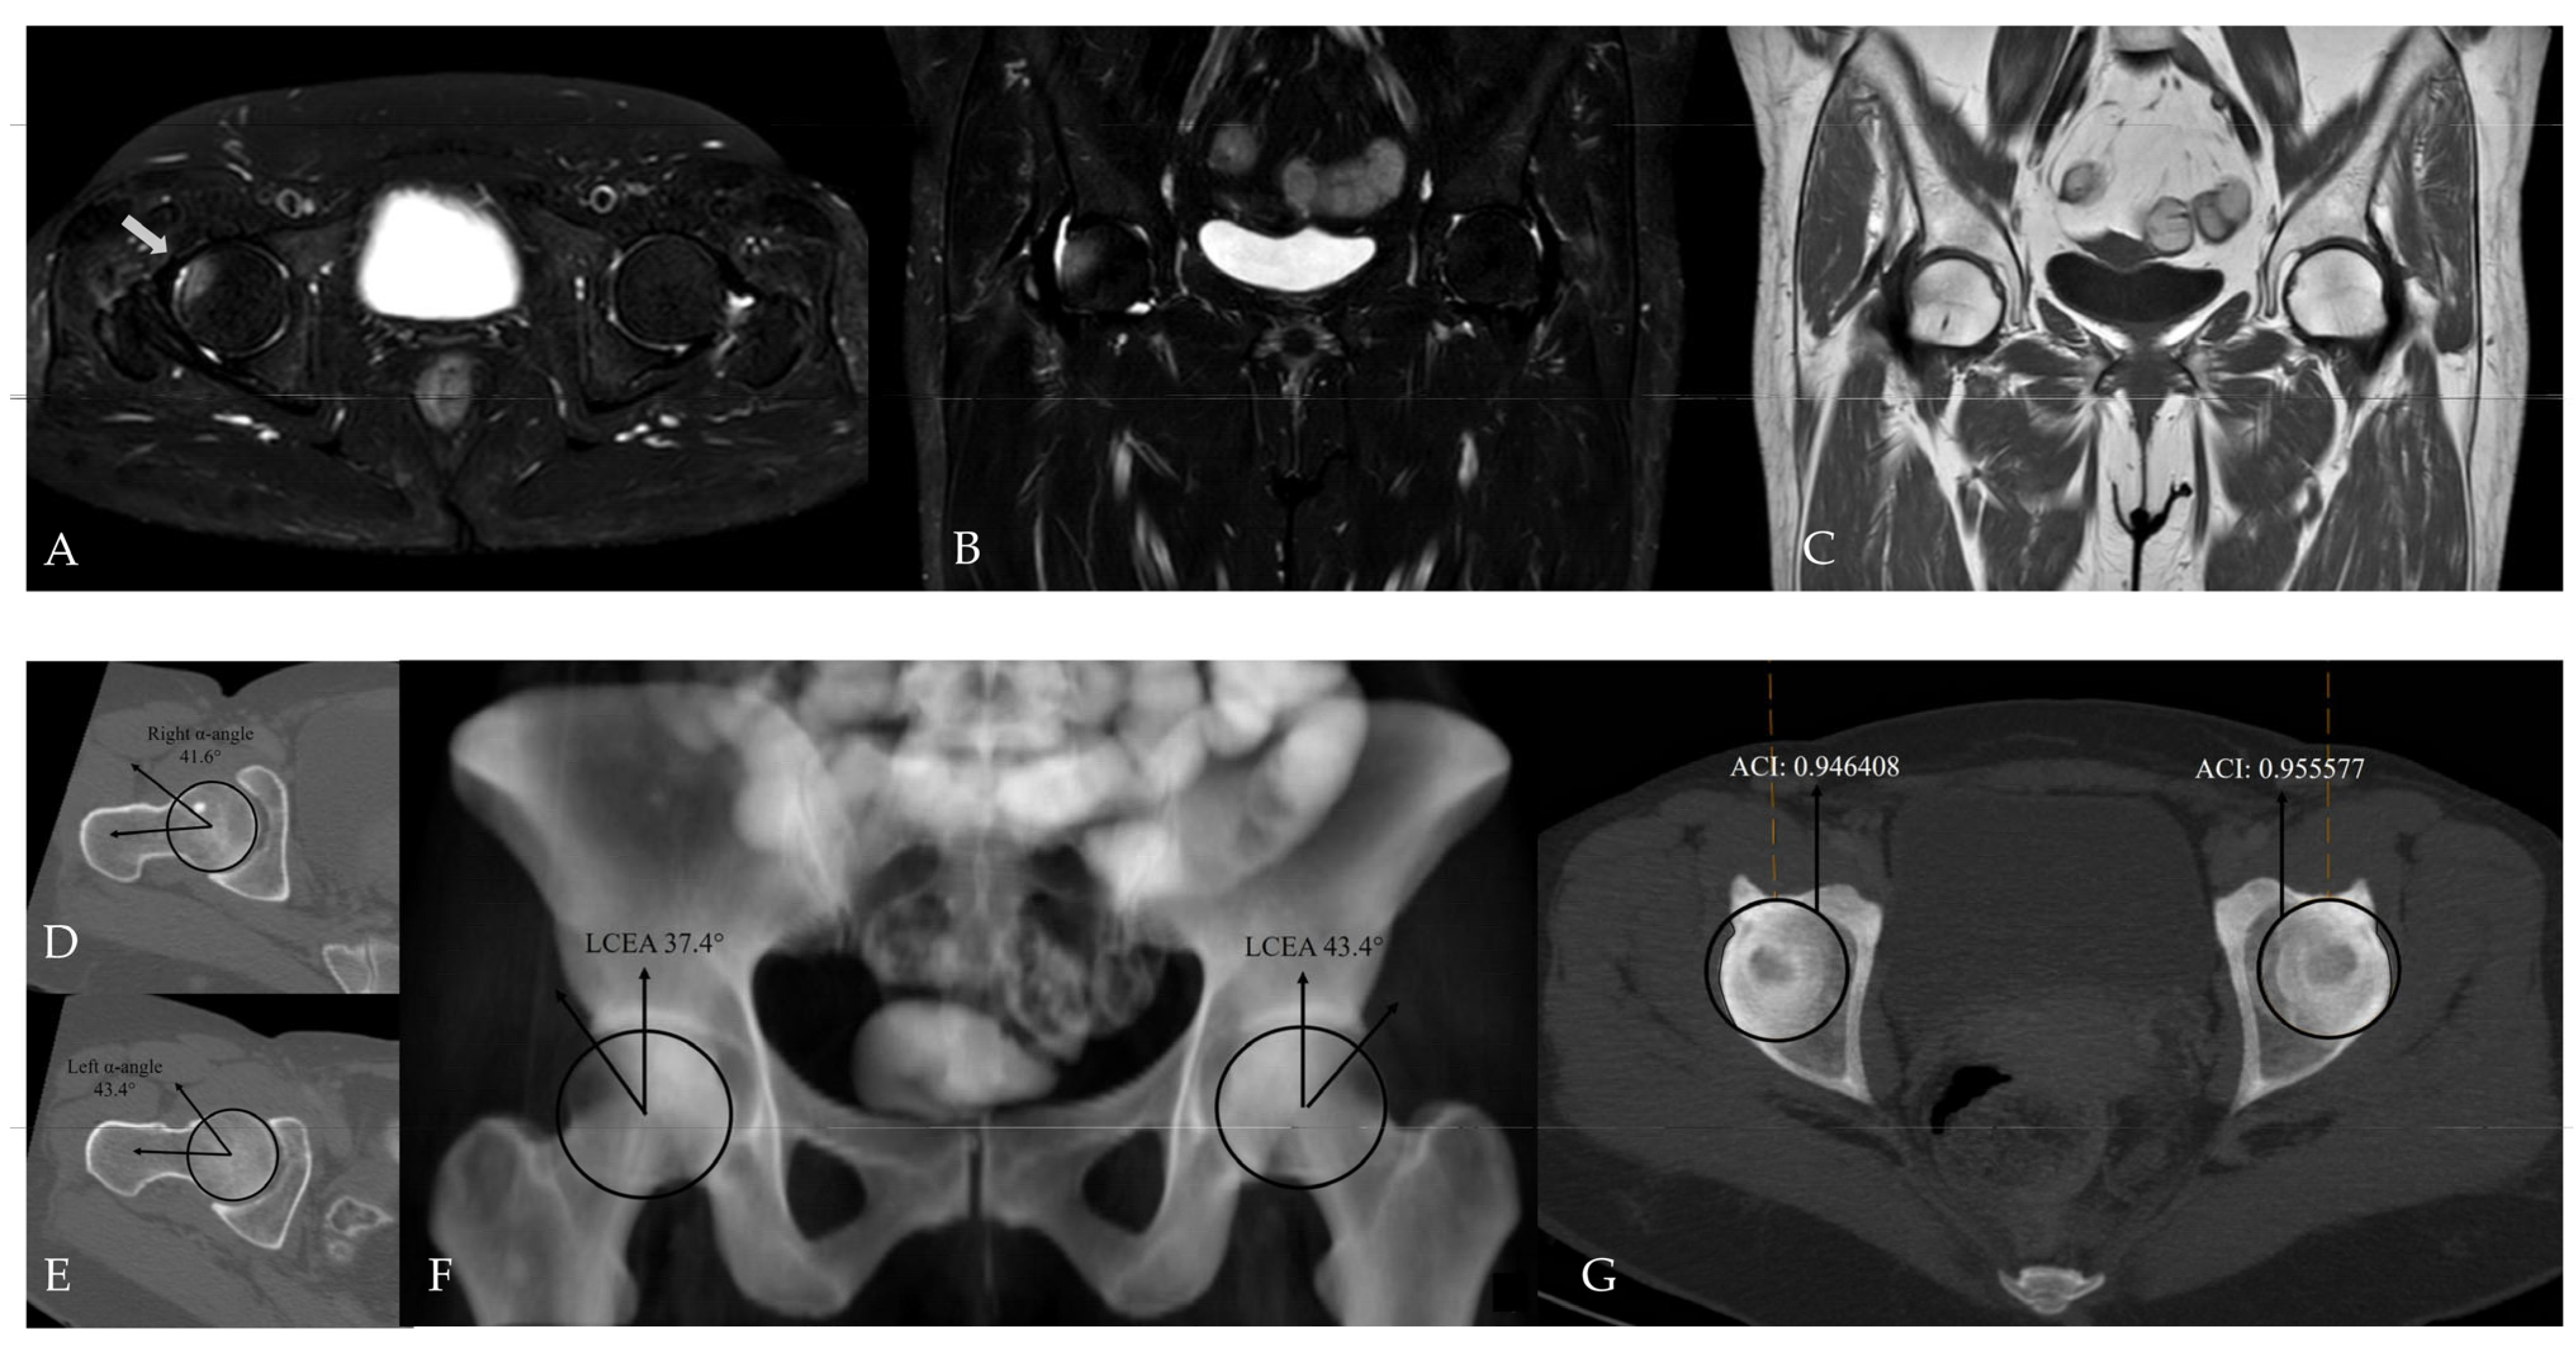

Figure 2. Application of conventional angular measurement methods on a radiology workstation. (A) Measurement of the alpha angle on axial oblique CT reformats. (B) Measurement of the LCEA on a CT-based virtual pelvic radiograph.

The alpha angle and lateral center–edge angle (LCEA) were measured on CT. The alpha angle was assessed on axial oblique CT reformats parallel to the femoral neck axis as described by Nötzli et al., and the LCEA was measured using the CT-based coronal three-dimensional (3D) virtual pelvis radiograph model as used by Ergen et al. [13,14]. Acetabular coverage index (ACI) values were subsequently calculated using CT-MIP reconstructions. In all cases, angular measurements were complemented by a comprehensive morphological assessment for the presence of FAI, including evaluation of the crossover sign, posterior wall sign, ischial spine sign, and anterior wall lateralization (Figure 2 and Figure 3). CT was further used to evaluate the morphology of the acetabular rim, and acetabular overcoverage subtypes were determined [15]. The presence of underlying FAI and its specific subtype were determined by two radiologists in consensus. All measurements were independently repeated by both radiologists at a four-week interval. The senior radiologist had 20 years of musculoskeletal radiology experience, whereas the general radiologist had 5 years of clinical radiology experience. Prior to the measurements, the general radiologist underwent a one-week training period under the supervision of the senior radiologist. Statistical analyses were performed using the measurements obtained by the senior musculoskeletal radiologist. To assess intraobserver reliability, the senior radiologist recalculated ACI measurements after a minimum interval of two months. Prior to initiating angular measurements, the entire dataset was reviewed and verified by an independent radiology resident after deletion of all previous measurements and anonymization of cases. Subsequently, cases were randomly ordered to minimize assessment bias and ensure objective analysis. For primary statistical analyses, measurements obtained by the senior musculoskeletal radiologist were used to reflect routine clinical practice, while the second reader’s measurements were used exclusively for interobserver agreement analysis.

Imaging data were retrospectively retrieved from the SECTRA PACS workstation (IDS7, version 24.2.16.6066; Sectra AB, Linköping, Sweden). Cam-type FAI was defined by an alpha angle of ≥60°, whereas pincer-type FAI was defined by an LCEA of ≥40° (Figure 4) [16,17,18,19]. For CT-MIP evaluation, the maximal cross-sectional area of the femoral head was initially measured on axial CT images using a circular region of interest (ROI). MIP reformatted images with a slab thickness of 10 mm were subsequently generated to enable a comprehensive single-slice evaluation of the acetabular roof. The acetabular coverage area was calculated by manual freehand delineation of the acetabular roof margins covering the femoral head, while preserving the femoral head contours. The ACI was defined as the ratio of the acetabular coverage area to the area of the femoral head (Figure 5).